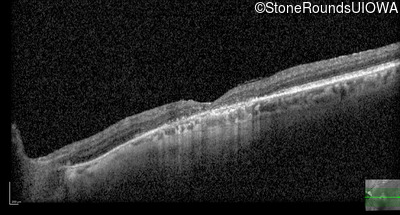

Optical Coherence Tomography - Right - 20/160

Exemplar / OCT Stack

OCT Stack